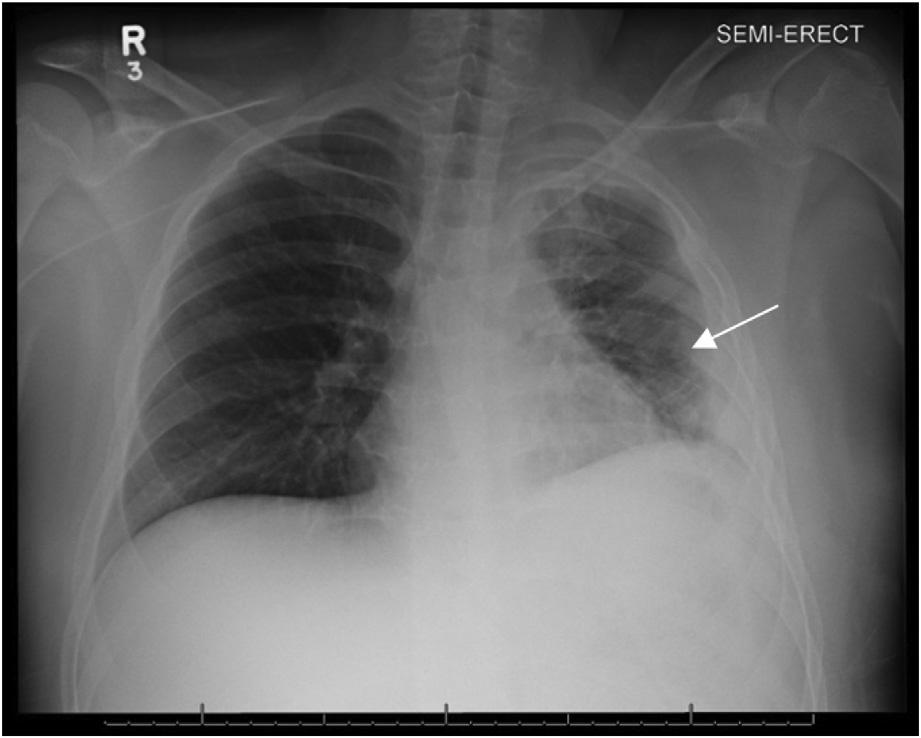

Duringhisinitialevaluationbyparamedicshedenied othercomplaints.Initialvitalswerepulse65beatsper minute,bloodpressure122/77millimetersofmercury,pulse oximetry100%onroomair,temperature36.6° Celsius,and respirations19breathsperminute.Hisphysicalexamwas significantforlethargy,althoughhewaseasilyarousableto voice;left-sidedchestwalltendernesstopalpation;bruising; crepitus;decreasedleftbreathsounds;andbilaterallower extremitypittingedema.Paramedicsobtainedbilateral anteriorviewsofthelung(Image1a),andimageswere interpretedinreal-timebythephysicianviaavideo

telehealthplatform.TheEPnotedtheabsenceoflungsliding intheleftinferiorlung field(Image1b).

Thepatientwasplacedon100%oxygenvianonrebreathermaskandtransportedtoalocalemergency department(ED).UponarrivalattheEDhedeniednew complaints,andhisvitalsandphysicalexamwerenot significantlychanged.Hiselectrocardiogram(ECG)showed anatrialsensedpacedrhythmconsistentwithpriorECGs. Hehadachestradiograph(CXR)showingleft fifthandsixth ribfractureswithamoderatecircumferentialpneumothorax (Images2 and 3).

Image1. (A)Exampleofacommunitytele-paramedicvisitwithvideoconferenceandscreensharingusingmobileultrasound.Thepatientis seenatthetop,andtheemergencyphysicianisseenonthebottomscreen.(B)Thecasepatient’sb-modelungpoint-of-careultrasound, showingaccentuateda-lines,lossofb-lines,andinreal-timevideowithoutlungsliding(notpicturedhere).

Image2. Chestradiographwitharrowspointingtoleft-sidedmoderatecircumferentialpneumothorax.Thereisalossofsymmetry,avisible lungborder,andlossoflungmarkingsuperiortothelungborder.

Image3. Magnifiedviewofthechestradiographdemonstrating fracturesofribs fiveandsix(arrows).